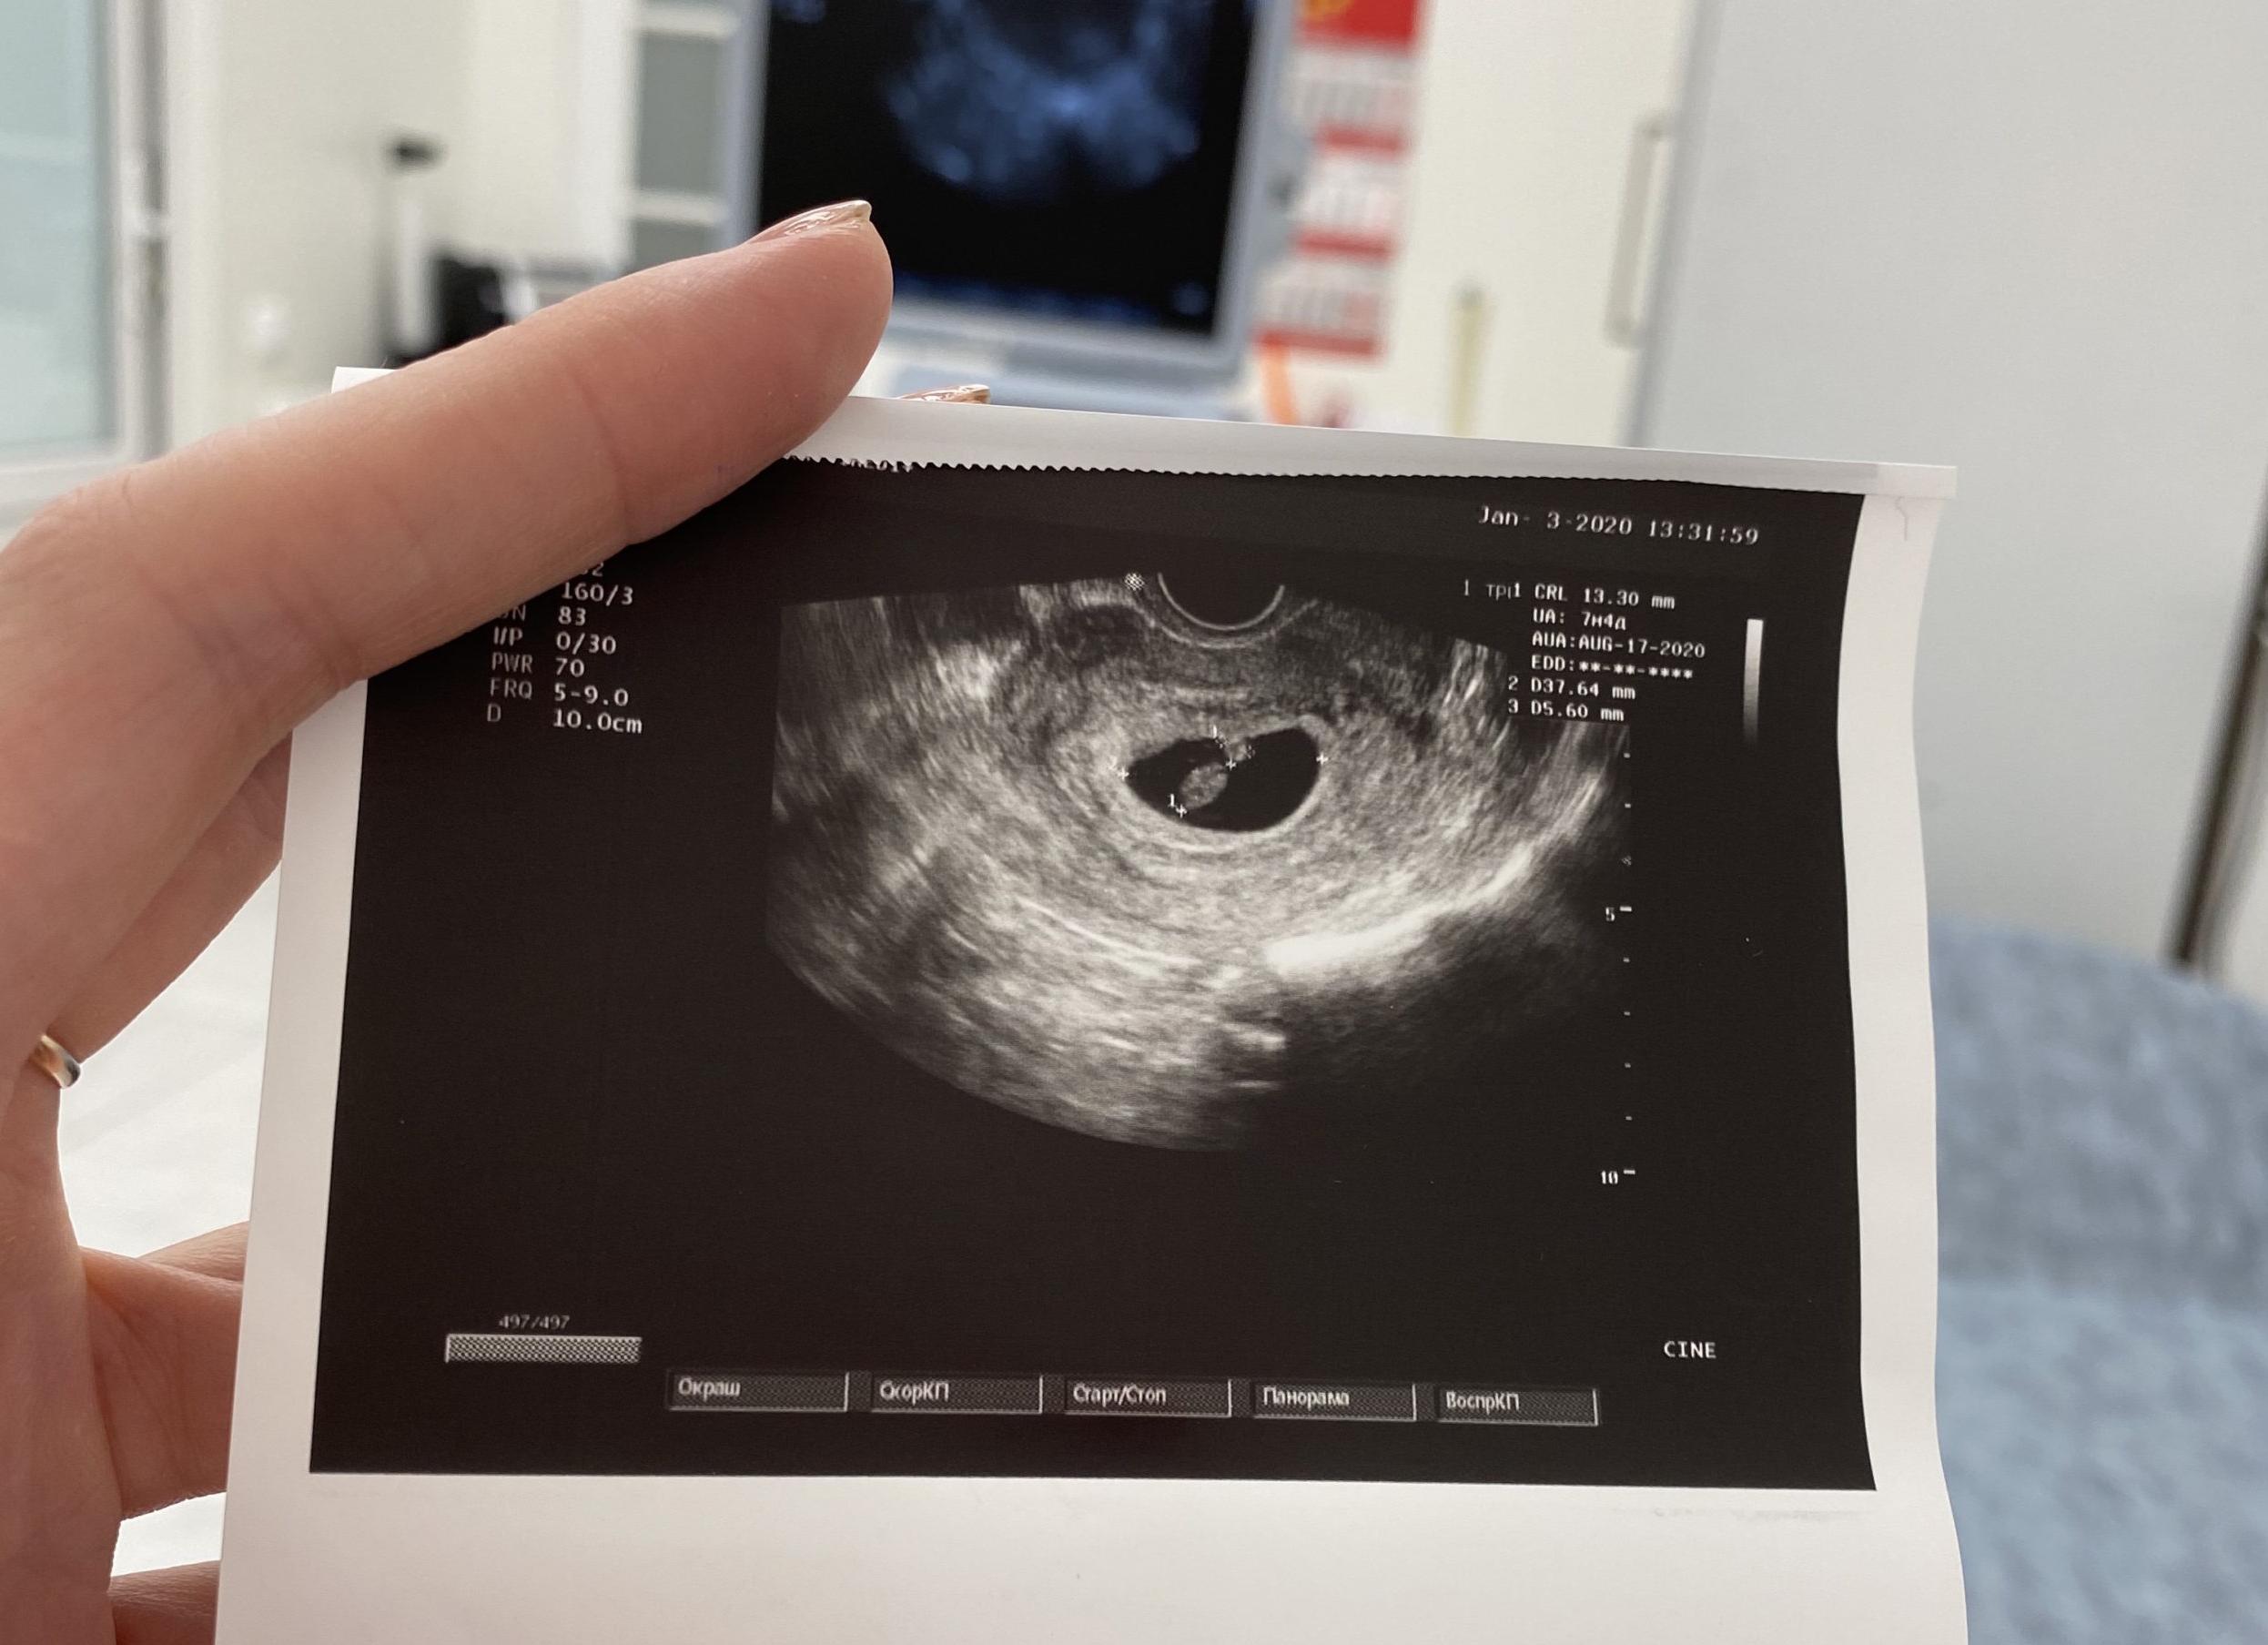

Первый скрининг или скрининг первого триместра предполагает комплексное обследование, которое проводится путем забора крови из вены и проведения УЗИ на сроке 11-14 недель. Он позволяет определить риск патологических изменений у плода, и, прежде всего, направлен на выявление пороков развития нервной трубки, синдрома Дауна и синдрома Эдвардса, грубых нарушений в развитии других органов и систем.

Первый скрининг могут провести также в том случае, если пара сама изъявит желание убедиться в том, что с их ребёнком всё в порядке. Процедура предполагает 2 исследования беременности — УЗИ и анализ крови (в данном случае её берут из вены).

Первый скрининг (скрининг первого триместра) проводится на сроке 11-14 недель, причем идеальным сроком является 12-13 неделя.Если быть точнее — начиная с первого дня на 10 неделе и заканчивая пятым днём 13-ой. Самый оптимальный срок для проведения исследований первого скрининга — середина указанного времени, т. е. приблизительно шестой день 11 недели. Более точно дату рассчитывает врач, назначающий анализы и ведущий беременность.В некоторых случаях срок первого скрининга может быть слегка увеличен до 6-го дня 14 недели, но тогда погрешность полученных данных будет более ощутимой, а результаты — не совсем точными.

- исследование УЗИ (причем, многие лаборатории запрашивают результаты УЗИ в обязательном порядке, без них расчеты не проводятся)

УЗИ исследование:

Результаты первого скрининга выводятся из УЗИ и данных, полученных в результате биохимии крови. Оба исследования дополняют друг друга и обеспечивают большую точность полученных показателей беременности.

Ультразвуковое исследование

УЗИ и анализ на биохимию крови проводятся в одной лаборатории. Сначала — ультразвуковое обследование, которое точно определит срок беременности. Отталкиваясь от этого показателя, лаборанты потом будут делать расшифровку двойного теста.

Трансвагинальное УЗИ предполагает введение датчика во влагалище. При трансабдоминальном УЗИ датчик контактирует с животом. Исследуемая область смазывается гелем для беспрепятственного прохождения волн, затем врач датчиком водит по телу. Изображение на мониторе компьютера позволяет увидеть, в каком состоянии находится плод, и сделать соответствующие замеры. Если положение ребёнка не позволяет врачу провести измерения, он может попросить женщину покашлять, походить, подвигаться, чтобы плод повернулся так, как нужно.